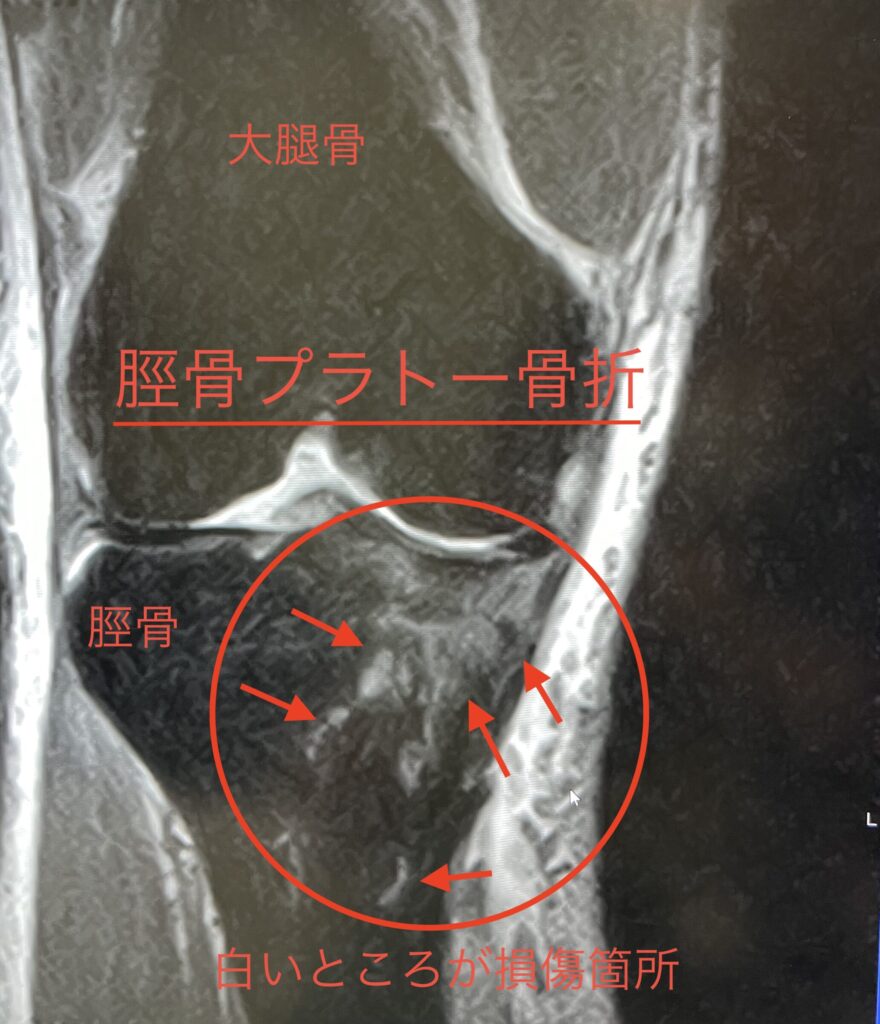

骨折の症状としては主に2つで一つは大腿骨で脛骨(けいこつ)を押し潰しちゃった脛骨プラトー骨折、もう一つは前十字靱帯のつけ根のところが剥離しそうになってる顆間(かかん)隆起骨折。

どちらもレントゲンでは殆ど映らなくてMRIじゃないと分からない状態(写真の丸で囲った所の白い部分が損傷箇所)でした。